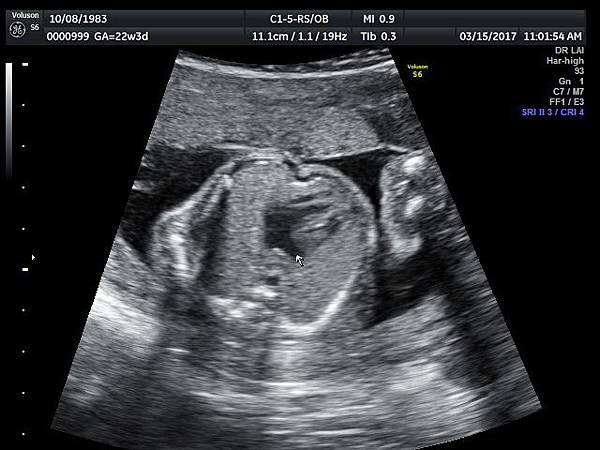

2017年3月15日33歲第一胎試管嬰兒懷孕22週3天的孕婦 、在我的診所接受胎兒心臟及高層次超音波檢查,檢查結果是單純持續性左側上腔靜脈(PLSVC),沒有合併其他異常(附圖 1~3),孕婦之前已經接受24000元的非侵入性染色體基因篩檢(NIPS),沒有異常發現,我的建議是追蹤檢查即可,如果真的很不放心,也可以考慮抽羊水做染色體及基因晶片檢查(array - CGH)。

39 22 weeks isolated PLSVC -2

38 22 weeks isolated PLSVC -1